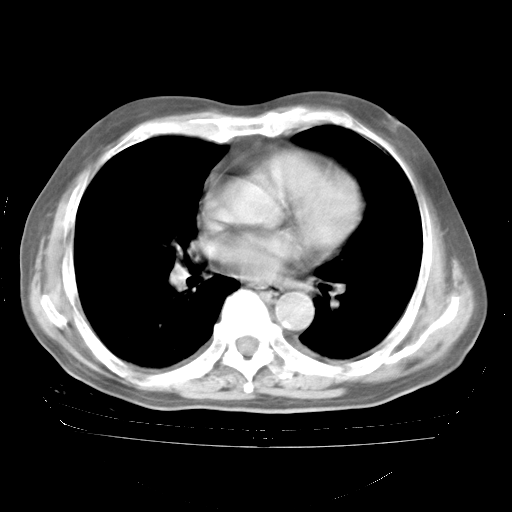

4月28日肺部CT——再次出现类似去年5月9日——透光度降低,“间质性”改变。

4月28日肺部CT——再次出现类似去年5月9日——磨玻璃样、间有“粟粒样”改变。